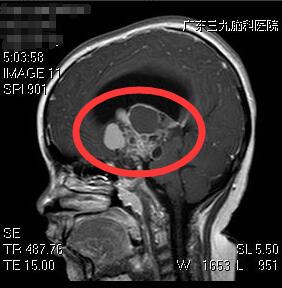

孩子术后肿瘤切除

5月22日,鲁明主任为患者在全麻下行巨大颅咽管瘤切除术。因肿瘤巨大,约5cm×5.6cm×7.7cm厘米,包裹了颈内动脉、大脑前动脉和中动脉,且肿瘤位于脑深部,钙化明显,质地坚韧,故手术难度极大。经过近12个小时的挑战,肿瘤被顺利切除。目前,小敏康复良好。

“肿瘤压迫了视神经和垂体柄,患者已出现脑积水,如不及时发现并进行手术,轻则症状加重,重则危及生命。”鲁明表示,患者5岁时的一些症状已提示颅内可能已有肿瘤,因未能及时发现和就医,导致肿瘤进一步长大及钙化,增加了手术难度和风险。